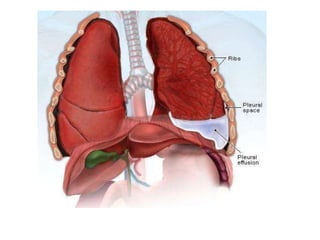

Pleural Disease Associated with

Asbestosis

 Pleural Plaques

 Pleural Thickening

 Pleural Effusion

 Mesothelioma

Pleural Effusions

 May persist for months-years

 Symptoms - chest tightness, pleuritic chest

pain, fever, dyspnea

 May reoccur on same side or opposite side

after yrs of exposure

 Effusions maybe bloody

Pleural Disease Associatedwith Asbestosis  Pleural Plaques  Pleural Thickening  Pleural Effusion  Mesothelioma

Pleural Effusions  Maypersist for months-years  Symptoms - chest tightness, pleuritic chest pain, fever, dyspnea  May reoccur on same side or opposite side after yrs of exposure  Effusions maybe bloody